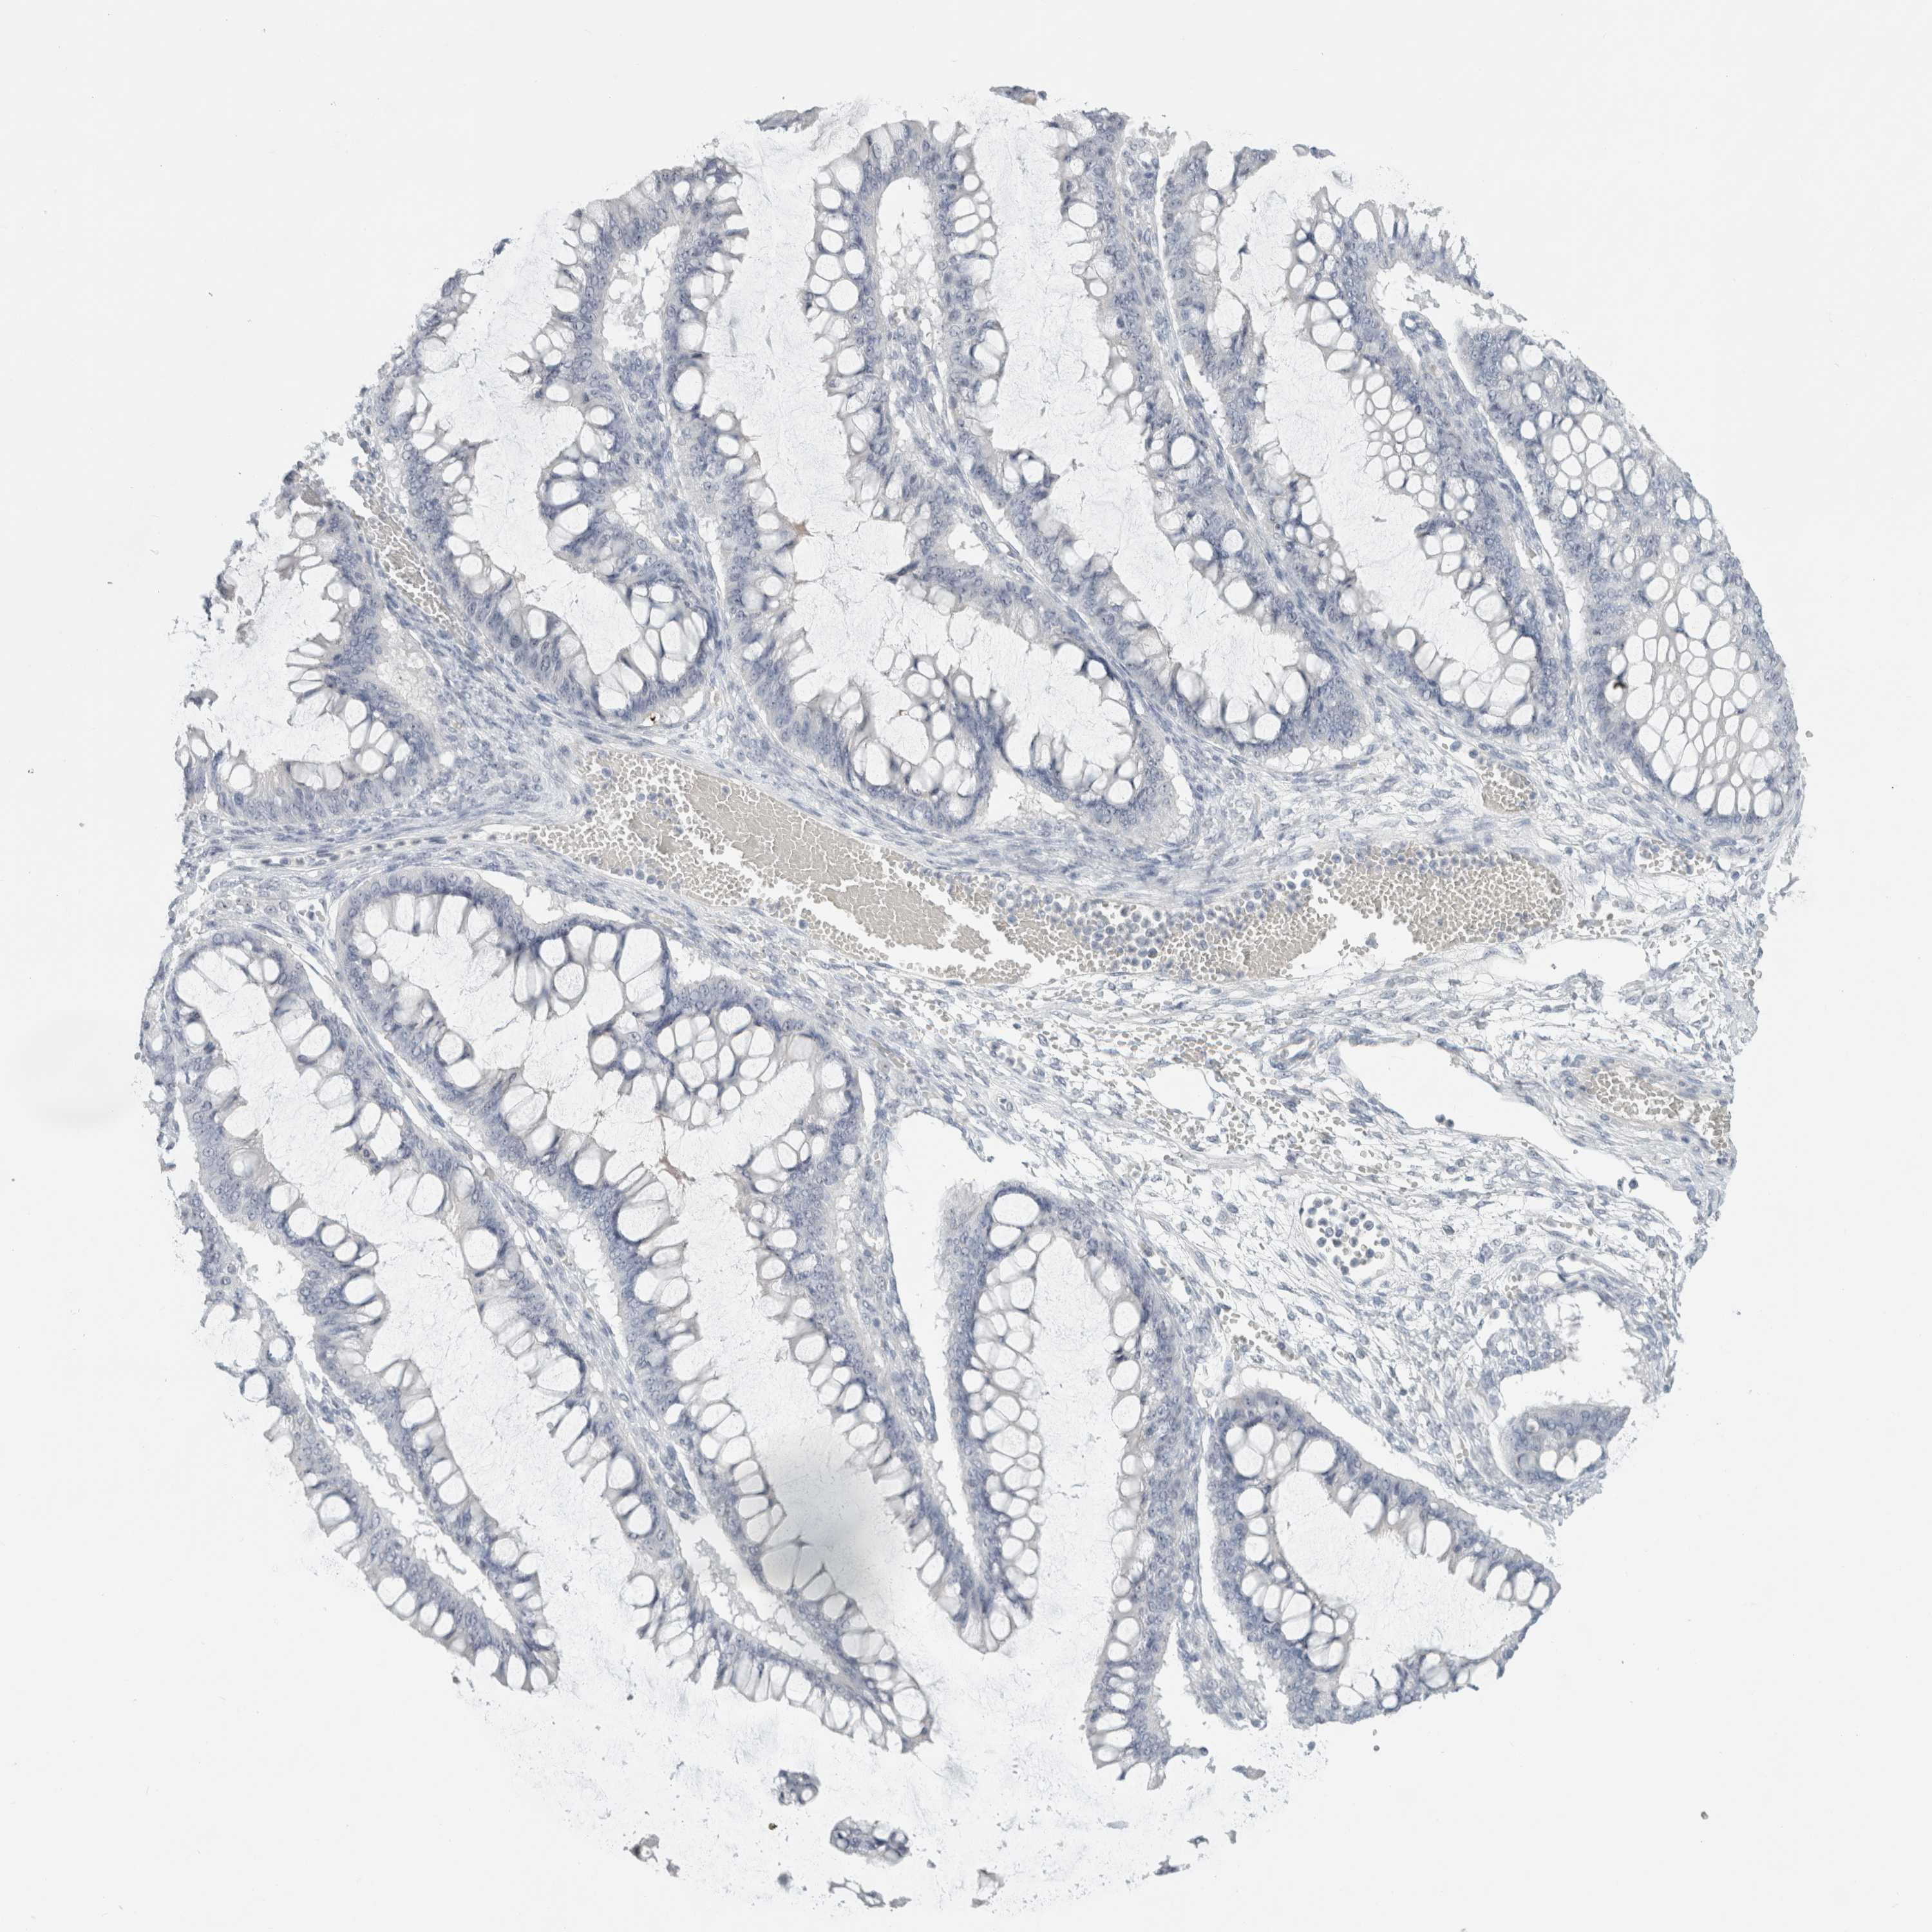

OVARIAN CANCER - Protein expressioni

A mouse-over function shows sample information and annotation data. Click on an image to view it in a full screen mode. Samples can be filtered based on level of antibody staining by selecting one or several of the following categories: high, medium, low and not detected. The assay and annotation is described here.

Note that samples used for immunohistochemistry by the Human Protein Atlas do not correspond to samples in the TCGA dataset.

Antibody stainingi

Antibody staining in the annotated cell types in the current human tissue is reported as not detected, low, medium, or high, based on conventional immunohistochemistry profiling in selected tissues. This score is based on the combination of the staining intensity and fraction of stained cells.

Each image is clickable and will lead to virtual microscopy that enables deeper exploration of all samples and also displays staining intensity scores, fraction scores and subcellular localization as well as patient and tissue information for each sample.

Antibody HPA011284

Antibody CAB026403

Cystadenocarcinoma, serous, NOS

Carcinoma, endometroid

Cystadenocarcinoma, mucinous, NOS

Carcinoma, NOS